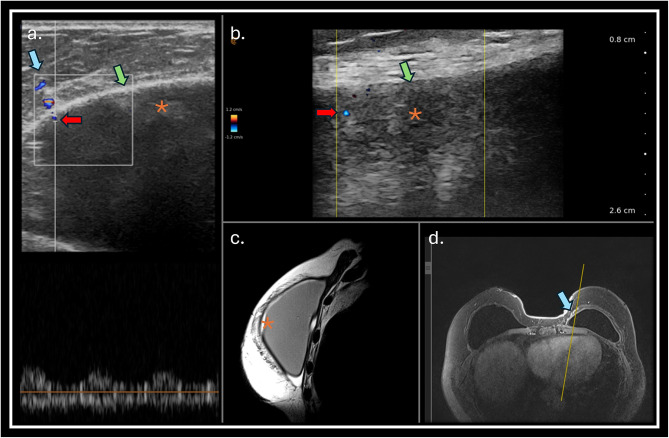

Materials and methods: A prospective observational study was conducted in a single center to evaluate breast implant complications in patients referred to breast magnetic resonance (MRI) scan. All patients who had breast implants submitted to MRI scan were invited to a complementary dedicated ultrasound (US) evaluation of the breast implants. The implant changes were classified following a dedicated protocol. The classifiers used to evaluate the implant include evaluation of implant surface (shell), implant internal content homogeneity, fibrous capsule, intracapsular space, pericapsular space, and axillary extension.

Results: Preliminary results included evaluating 29 consecutive patients who underwent MRI. Twenty-nine patients with 49 implants were included in the study. The US showed a superior ability to assess the internal contents of the implants, the implant surface, and the intracapsular contents. There were no significant statistical differences in evaluating macro changes such as implant location, intracapsular collection, and radio-frequency identification (RFID) presence. MRI was superior to the US in classifying the fibrous capsule type.